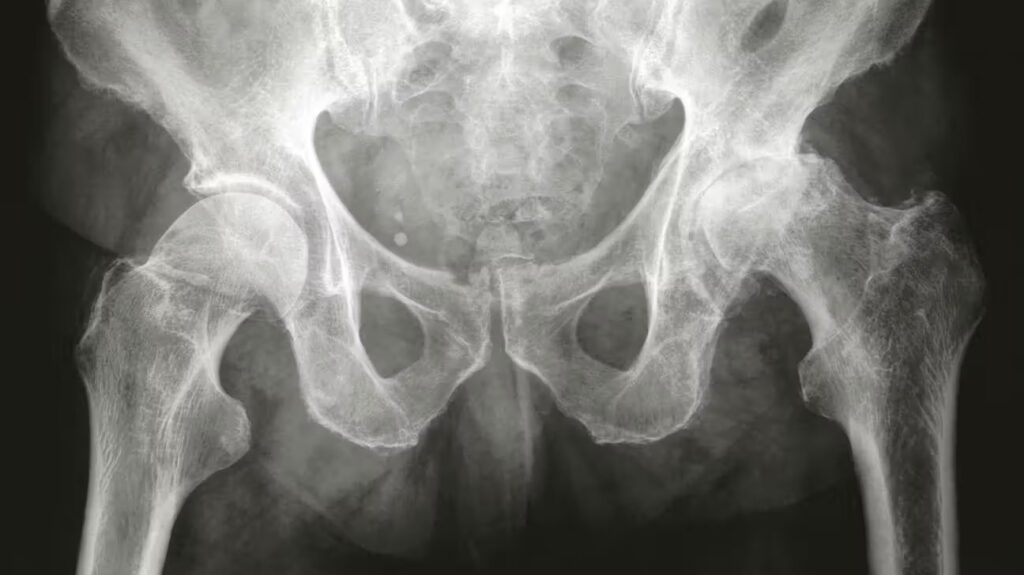

Hip arthritis occurs when the protective cartilage lining the hip joint gradually wears away. This causes the bones in the joint to rub together, leading to pain, stiffness, inflammation, and progressive loss of movement. While osteoarthritis is the most common form, other underlying conditions can also lead to degenerative changes in the hip.

Osteoarthritis of the hip is the most common form of arthritis affecting the hip joint. It involves the progressive loss of cartilage, the smooth, protective tissue that allows the joint to glide comfortably. As this cartilage deteriorates, the joint becomes inflamed and painful. The condition is becoming more common due to our ageing population, but it can affect younger adults as well, particularly those with underlying joint abnormalities or a history of trauma.

Cartilage damage triggers an attempted repair response from the body. Unfortunately, cartilage cannot regenerate itself effectively, leading to chronic inflammation inside the joint and worsening symptoms over time.

• X-rays: To assess the joint space, cartilage loss, and signs of bone changes such as osteophytes or femoral head deformity.